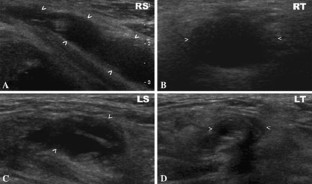

Figure 1